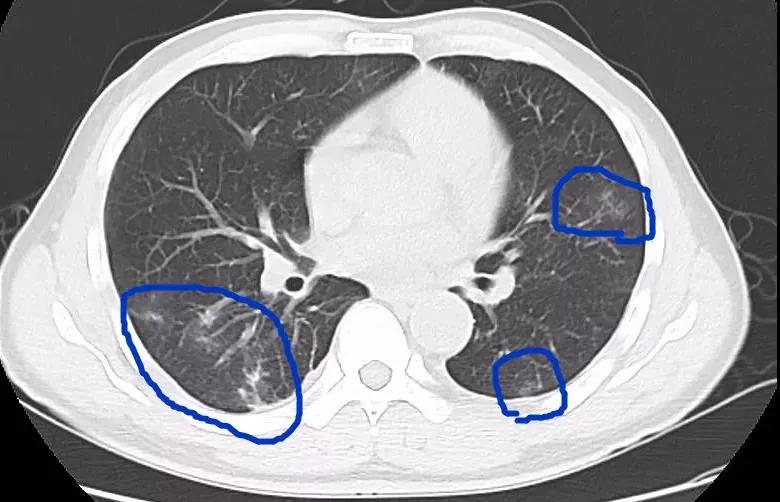

近日,深圳一家三口品尝了美味的醉蟹1个月后,先后出现了发热、腹痛、干咳等症状,他们到医院检查后,发现血常规中嗜酸性粒细胞明显升高,随即进行进一步的寄生虫抗体、CT等检查,最终三人均被确诊为“肺吸虫病”。

并殖吸虫寄生在肺部,常会引起咳嗽、胸痛、咳铁锈色痰等;虫体在腹腔脏器间移行,引起腹痛、腹泻、恶心、呕吐等症状,侵犯肝脏可致肝功能异常;如果虫体侵入大脑,更会出现头痛、头晕、癫痫、感觉异常等;此外,也可表现为皮下结节或包块。